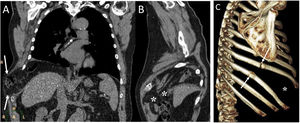

A 72-year-old man with a pulmonary nodule in the right upper lobe. Percutaneous fine needle (22 G) lung puncture cytology was of a non-small cell lung neoplasm. A and B) The chest X-ray 72 h after the procedure revealed signs of pneumomediastinum and significant subcutaneous emphysema (white arrows). The biopsied pulmonary nodule can be seen in the periphery of the right upper lobe in the posteroanterior view of the chest X-ray (black arrows). B and C) Computed tomography confirmed pneumomediastinum and subcutaneous emphysema and showed predominantly left bilateral pneumothorax (white arrows) with communication between both pleural spaces in the anterior junctional line (black arrows), probably of congenital origin, since there was no previous thoracic surgery. The subcutaneous emphysema was drained through an incision in the chest wall and multiple pleural adhesions were identified during the surgical procedure of right upper lobectomy.

A 55-year-old man with a mass on the right chest wall of more than two years of evolution. A) Computed tomography (multiplanar reconstruction in coronal and sagittal planes) revealed a right transdiaphragmatic intercostal hernia with colon and abdominal fat (white arrows). C) Multiplanar reconstruction in the sagittal plane enabled identification of the diaphragmatic defect (white asterisks). B) The 3D (sagittal plane) showed fracture calluses in the lateral arches of the eighth and ninth right ribs (white arrows) with widening of the intercostal space (white asterisk).